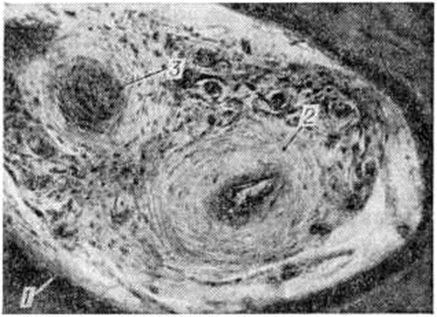

Пародонтоз может протекать с преимущественным развитием в околозубных тканях дистрофических изменений с характерной атрофией костных трабекул губчатого вещества, выраженным очаговым остеосклерозом, чередующимся с очаговым остеопорозом (рисунок 1). Патологический изменения в костной ткани сочетаются с выраженными изменениями её кровеносных сосудов: гиперплазией внутренней оболочки, склерозом и гиалинозом средней оболочки, резким сужением или полной облитерацией просвета сосудов (рисунок 2). В соединительнотканной основе десны также отмечаются выраженные изменения сосудов, проявляющиеся пролиферацией эндотелия, образованием пристеночных тромбов, иногда развитием картины васкулита; на этом фоне довольно часто наблюдается набухание коллагеновых волокон, их фрагментация и даже лизис. В целом состояние десны характеризуется развитием в ней вялотекущего воспалительного процесса, в соединительнотканной строме десны обнаруживают инфильтраты из плазматических и лимфоидных клеток, локализующиеся преимущественно в области десневой борозды.